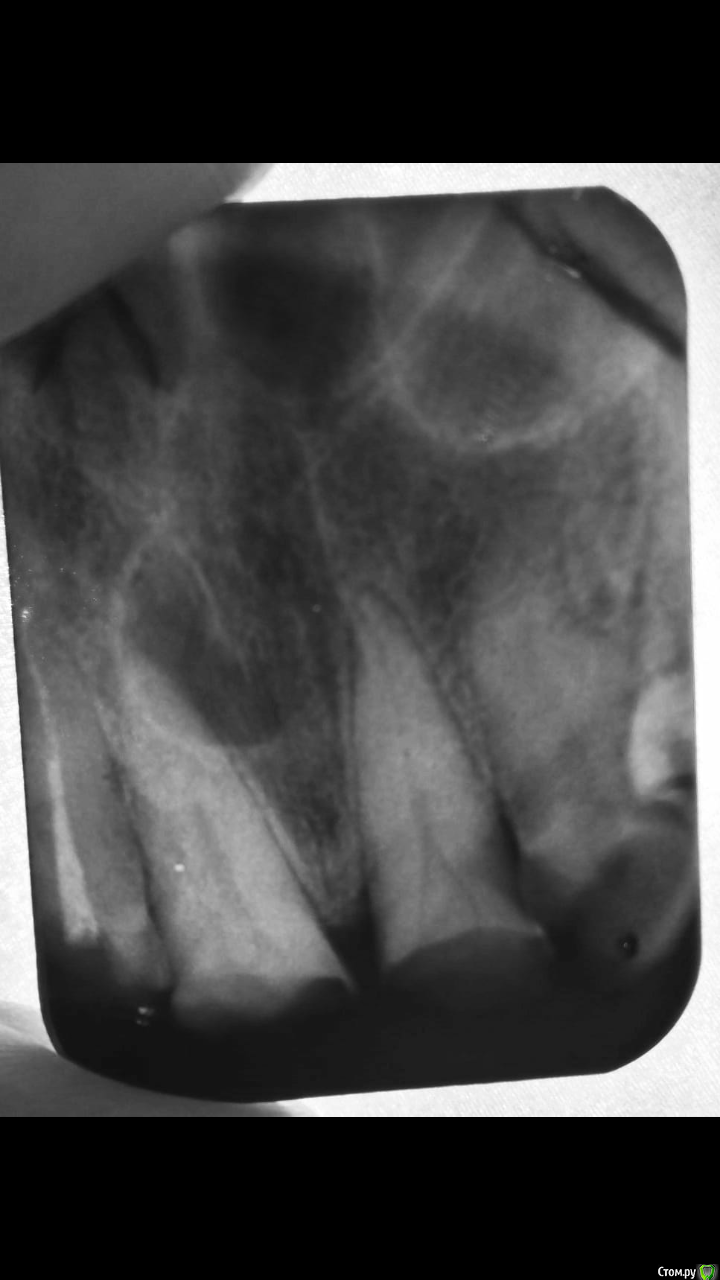

stomatpavel Опубликовано 16 апреля, 2019 Поделиться Опубликовано 16 апреля, 2019 (изменено) Добрый день коллеги, обратился пациент с целью подготовки под ортопедическое лечение. Необходимо депульпировать 1.1 и 2.1. И тут самое интересное для меня это на прицельном снимке. И также форма канала, который начинался двумя устьями и по ходу разработки слился в один. Доктора, прошу совета что это может быть (пациент отказывается делать кт). Переделали прицельный снимок и ситуация повторилась. Это может быть киста резцового канала или связана с зубом? Или это периодонтит? Как поступить с зубом 2.1? Во рту отмечается пат. стираемость и двухсторонний дистально неограниченный дефект зубного ряда. Спасибо) Изменено 16 апреля, 2019 пользователем stomatpavel Ссылка на комментарий

___49___ Опубликовано 17 апреля, 2019 Поделиться Опубликовано 17 апреля, 2019 (изменено) Дентикли уберите из устьевой части обоих зубов , и будет Вам счастье . (это третичный дентин в пульповой камере из-за пат.стираемости). резцовый канал не трогайте - пусть будет . Изменено 17 апреля, 2019 пользователем ___49___ 3 Ссылка на комментарий

vse32 Опубликовано 17 апреля, 2019 Поделиться Опубликовано 17 апреля, 2019 резцовый канал не трогайте - пусть будет А что тогда обозначает на снимке "кругленькая хрень"? Ссылка на комментарий

___49___ Опубликовано 17 апреля, 2019 Поделиться Опубликовано 17 апреля, 2019 (изменено) А что тогда обозначает на снимке "кругленькая хрень"? "кругленькая хрень" своими размерами в пограничном состоянии ( порядка 6мм) для того чтоб назваться кистой , диагноз поставить можно либо по КЛКТ , либо клинически ( постоперационный диагноз) как я понимаю пациент отказывается что либо из этого делать, доктор ему уже объяснил и он проинформирован (в карточке отказ, подпись ) на данный момент у Павла стоит задача подготовить зубы, пусть готовит (периодонтальная щель судя по снимку классически с "каналом-кистой" не сообщается ). если потом этого пациента все же жареный петух догонит , то с большей долей вероятности хирург отработает небно , без каких либо последствий для ортопедической конструкции и каких-то проблем со стороны пролеченных единичек( если конечно все будет пролечено как положено ) . ... P\S: Если бы пациенты разделяли со мной , взгляды в необходимости того или иного метода лечения или диагностики ..... Но к сожалению есть "товарисчи" которые думают , что с остеомиелитом ходить лучше , чем шинироваться, что подчелюстная флегмона с свищями в одноименной области тоже может подождать оперативного лечения, или явное ЗНО - это все выдумки врача (мои) с ним (пациентом) такого просто не может быть . ..а ведь с ними разговариваешь почти как с детьми , все по полочкам , на ложечку в рот.... Боюсь у ТС подобный пациент, максимум , что может сделать терапевт для установки точного диагноза он уже сделал - предложил КТ , пациент отказался( предположения есть - диагноза нет) Изменено 17 апреля, 2019 пользователем ___49___ Ссылка на комментарий

vse32 Опубликовано 17 апреля, 2019 Поделиться Опубликовано 17 апреля, 2019 Я помню что отказ. Я для себя спрашиваю. Если вдруг увижу такое у своего пациента - могу ли я предварительный диагноз "киста носонебного канала" поставить? Ссылка на комментарий

___49___ Опубликовано 17 апреля, 2019 Поделиться Опубликовано 17 апреля, 2019 Я помню что отказ. Я для себя спрашиваю. Если вдруг увижу такое у своего пациента - могу ли я предварительный диагноз "киста носонебного канала" поставить?Все верно , классический вариант - обосновываете направление пациента к хир.стоматологу предварительным диагнозом "киста носонебного канала" ? а там как говориться уже разберутся. (киста по хорошему - гистологический диагноз) . Ссылка на комментарий

stomatpavel Опубликовано 18 апреля, 2019 Автор Поделиться Опубликовано 18 апреля, 2019 (изменено) Добрый день, пациента удалось направить на кт. Будем ждать информации) Вот еще один прицельный снимок, пока ждем... Изменено 18 апреля, 2019 пользователем stomatpavel Ссылка на комментарий